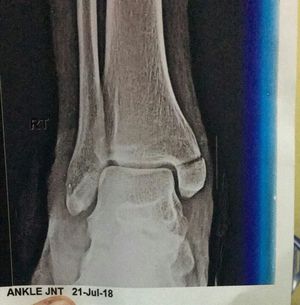

Which type of fracture??

Is it pott's fracture?

Its medial malleolus ,the pott is 6-7 cm above the medial malleolus.

Does proximal fibula have fracture too?

Medial malleolus is fractured of tibia but fibula shows no fracture 🤔